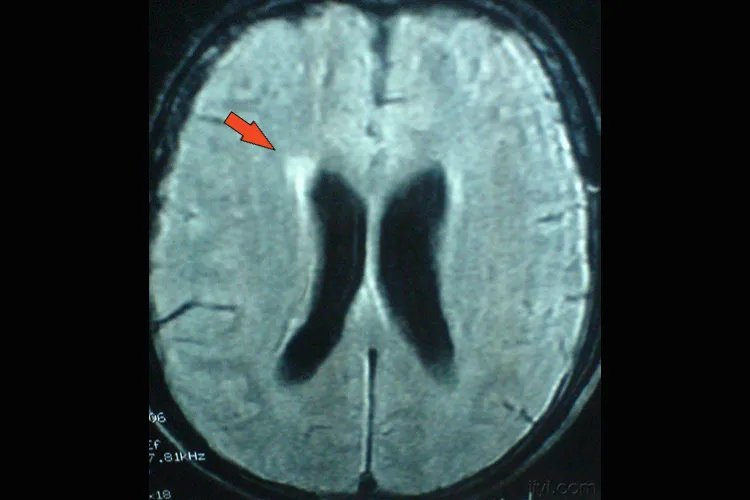

的有关信息介绍如下:概述脑膜炎CT表现为片状或斑点状的低密度影,或为不规则的结节状强化形态,常见病毒性脑膜炎、新型隐球菌脑膜脑炎、结核性脑膜炎。CT表现脑膜炎分析有病毒性脑膜炎、新型隐球菌脑膜脑炎、结核性脑膜炎等多种疾病形式,疾病不同其具体的影像表现如下:病毒性脑膜炎CT平扫表现为片状低密度影,伴轻度占位效应;增强检查,病变为不均匀强化,常呈双侧对称或不对称性分布。